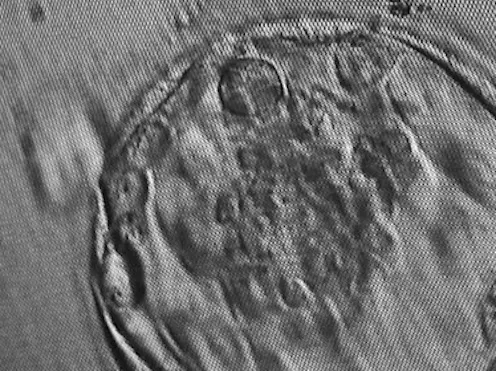

The researchers then grew these cells in 3D clusters for six days, after which some of them formed structures very similar to “blastocysts” — the final stage of embryonic development before implantation. These lab-grown structures are dubbed “iBlastoids”.

While iBlastoids and blastoids both seem to be structurally and functionally similar to real blastocysts, it is not yet clear exactly how closely they resemble true embryos formed by a sperm and an egg. While the models were shown to share gene patterns and respond in culture in ways characteristic of actual embryos, researchers also saw significant anomalies, such as unsynchronised growth and cells that are not usually present in an embryo.